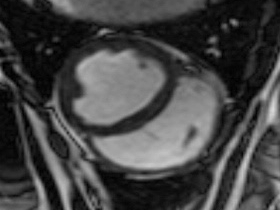

Easy-Trigger ist ein Medizinprodukt für die Herz- und Gefäßbildgebung in der Magnetresonanztomographie (MRT), das bifunktional bei Ungeborenen und Erwachsenen eingesetzt werden kann. Als weltweit erstes und einziges MRT-taugliches Doppler-Ultraschallgerät ermöglicht es erstmals Kombinationsuntersuchungen von MRT und Ultraschall. Der Ultraschallkopf wird auf dem Bauch oder über dem Herzen des Patienten platziert. Es ermöglicht erstmals die zeitliche Abstimmung der Herzaktion von ungeborenen Kindern mit dem MRT und damit MRT-Untersuchungen des kindlichen Herzens. Des Weiteren kann es zur Überwachung der Ungeborenen bei MRT-Untersuchungen von Schwangeren eingesetzt werden. Durch die Verwendung der Doppler-Ultraschall-Technik ist die Anwendung am Erwachsenen im Vergleich zum EKG robuster, einfacher und sogar bei höheren Feldstärken einsetzbar, bei denen das EKG nicht mehr zuverlässig arbeitet.

Cardiac MRI of the Fetal Heart Using a Novel Triggering Method: Initial Results in an Animal Model.

J Magn Reson Imaging. 2012 May;35(5):1071-6.